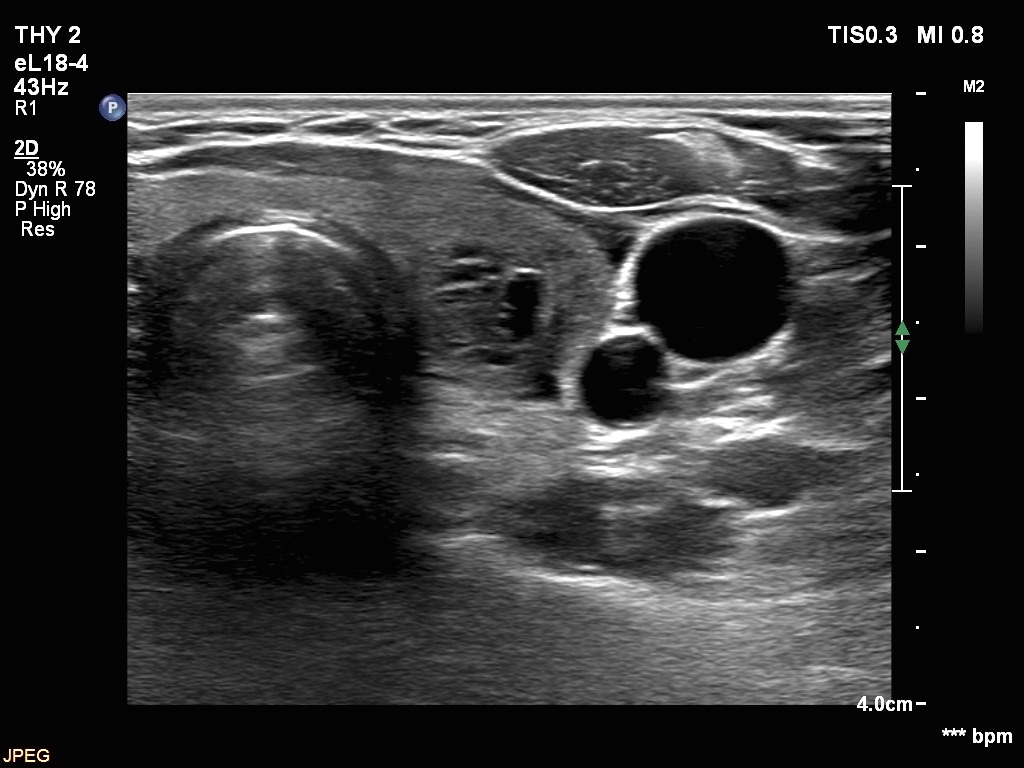

Ultrasonography. The thyroid was echonormal. There were two nodules in the right lobe. The upper was hyperechogenic-cystic while the lower was a minimally-moderately hypoechogenic. The latter had irregular, lobulated margins. There was a hypoechoic area in the upper two-third of left lobe. The discrete area presented ill-defined margins and decreased vascularization. A spongiform cyst was found in the lower pole of the left lobe.

Cytology of the nodule with irregular margins resulted in benign lesion, while cytology disclosed de Quervain's thyroiditis in the event of the hypoechoic area in the left lobe.